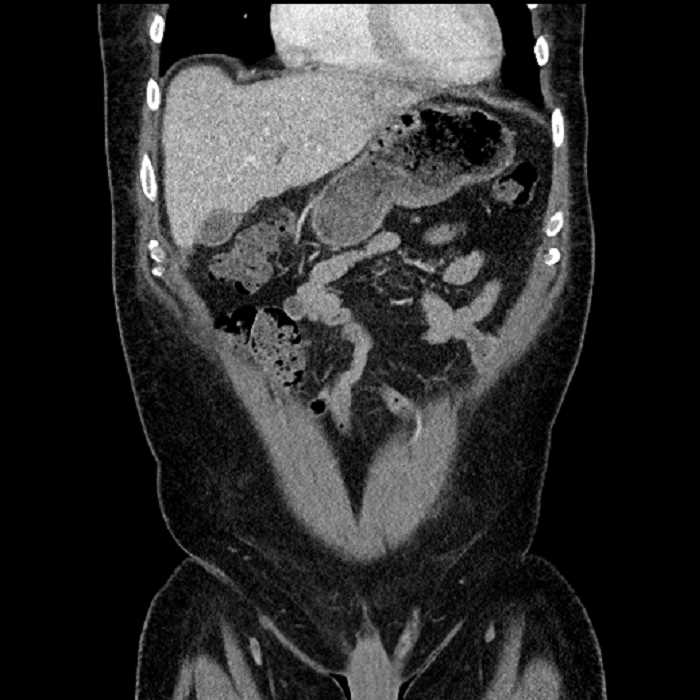

• Large fluid density structure in hepatic segments 7 and 8 measuring 10 x 7 x 7 cm with internal septation and circumferential ill-defined low density compatible with edema

• Peripherally enhancing subcapsular collections along the anterior margin of the left hepatic lobe measuring 3 x 1 cm and 2 x 1 cm

• Clearly marginated fluid density structure in segment 7 and several other scattered tiny hypodensities, which likely represent cysts

• Hepatic abscess

Acute sigmoid diverticulitis complicated by a small contained perforation and a large abscess in the right hepatic lobe. Additional small subcapsular abscesses along the anterior margin of the left hepatic lobe.

• The classic CT imaging appearance is a double target sign with internal low density surrounded by an internal enhancing rim (capsule) and a low density external rim (edema)

• Abscesses may be unilocular or multilocular

Hepatic abscess showing the double target sign with low density internally surrounded by a thin inner enhancing rim (red arrow) and ill-defined outer low density rim (yellow arrow). Blue arrow indicates an internal septation. Red arrows: additional smaller subcapsular abscesses. Red arrow: focal contained perforation associated with diverticulitis.